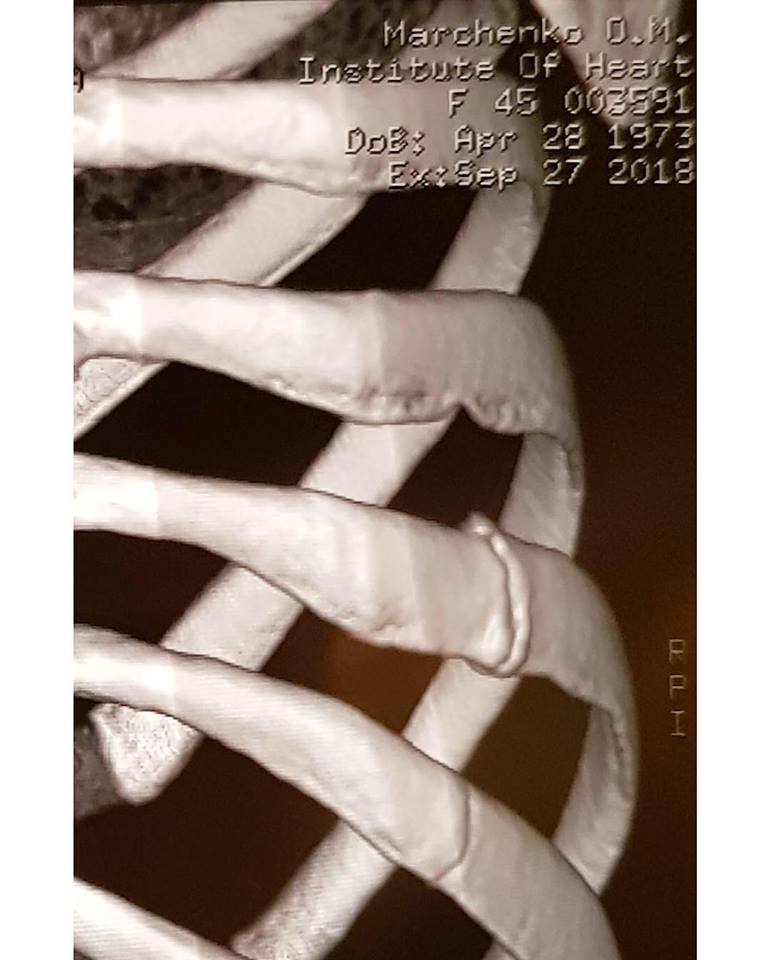

Телеведущая сообщила, что покидает проект после того, как выяснилось, что у нее сломаны два ребра. Травму она получила во время подготовки к прямым эфирам, на репетиции. Она ощутила острую боль, но подумала, что сильно потянула связки или мышцы. Первое время она принимала обезболивающее и продолжала репетировать и выступать на прямых эфирах. Но в итоге пришлось принять решение уйти из шоу, поскольку из-за усложняющейся программы врачи опасались рецедивов, ведь ткани в местах переломов еще достаточно слабые.

"А я не могу и не хочу работать вполсилы. До последнего времени об этой истории никто не знал, но сегодня я хочу быть искренней. Я победила свою боль, свои страхи и неуверенность. Мною гордится моя семья, мои родители, друзья, и я от всего сердца хочу их поблагодарить за поддержку и любовь", - написала телеведущая.

Она поблагодарила всех, кто за нее болел, семью и всех, кто делает шоу. И отдельно  своего партнера по танцам Дмитрия Чаплина. К посту Оксана Марченко приложила флюорографию ребер и медицинские справки, подтверждающие перелом двух ребер. А также фото с Дмитрием Чаплиным.